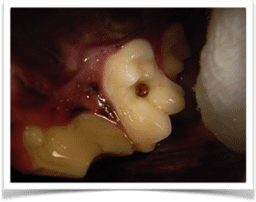

Minor and severe cavities affecting the maxillary first molar tooth.

Caries manifest from bacteria penetrating the enamel and work to destroy the dentin within the tooth, eventually involving the pulp cavity. When the veterinarian performs an oral exam with a dental probe explorer, the cavity will feel soft and sticky. They form by a process called “inorganic demineralization” of the enamel, which is started by the fermentation of plaque bacteria in the oral cavity.

Depending on the progression of the cavity, pulp exposure can occur. The pulp is living tissue on the inner aspect of the tooth. Dental radiographs and cone beam CT imaging allow us to visualize better how the cavity may be affecting the tooth.